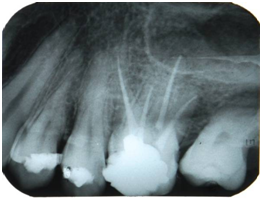

A male patient, melanoderm, aged 28, was referred to the Dental school clinic of the Federal University of Pernambuco seeking perform endodontic treatment of the tooth 26. The patient reported a throbbing and located pain in the tooth, which did not cease with the use of painkillers. After clinical and radiographic examination, it was found that there was an extensive temporary restoration in contact with the pulp chamber (Figure 1). The diagnosis was made with the cold testing of the pulp vitality, using the Endo Ice (Maquira, Brazil), which had a positive response, intense and prolonged, and the vertical percussion test was also positive. The diagnosis was irreversible pulpitis, establishing the need for endodontic treatment. Initially, the terminal infiltration anesthesia was performed and the absolute isolation with rubber dam clamp 201 (Duflex, SSWhite, Pennsylvania, USA). The next step was the access surgery with the diamond bur, round, number 1016 (KG Sorensen, São Paulo, Brazil) coupled to a high speed pen and, the divergence of surrounding walls was obtained with the Endo-Z (Maillefer, Ballaigues , Switzerland). The entry holes of the root canals were located using the explorer No. 47 (Duflex, SSWhite, Pennsylvania, USA). After exploration of the root canals with Flexofile #10 and #15 (Dentsply, Maillefer, Ballaigues, Switzerland), four independent root canals were located, two of them buccal and two palatal (Figure 2).

Figure 2 Maxillary molar with four roots: Instruments placed in their positions.